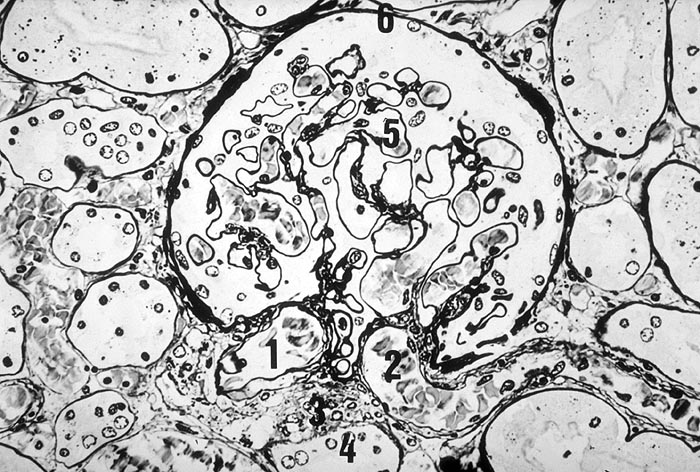

• Verbreiterung des Mesangiums mit Ausbildung von Knoten(noduläre Glomerulosklerose).

• Exsudative Läsionen: Hyaline Schlingenkappen (Proteinthromben in Glomerulumschlingen, im virtuellen Präparat nicht sichtbar) und Kapseltropfen (Proteinablagerungen im Bowman’schen Kapselraum).

• Arteriolosklerose von Vas afferens und efferens (Gefässwandhyalinose durch Ablagerung von Plasmaproteinen und Lipiden in der Gefässwand).